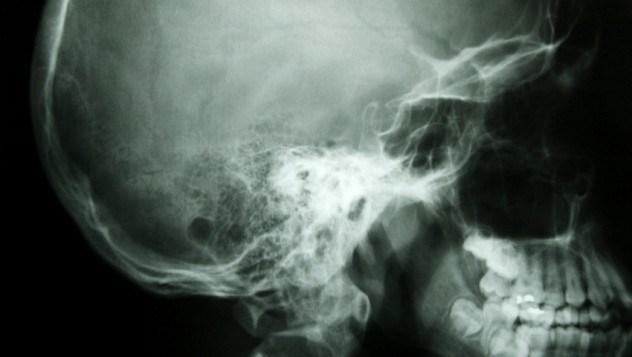

7 Tekila rešila dečka

Ko se je 13-letni Evan Hamilton odpravljal proti šoli, so ga sošolci izzvali naj spije osem štamprlov tekile. Hamilton je z veseljem praznil steklenico, kasneje pa v šoli padel v nezavest. Takoj so ga odpeljali v bolnišnico in po skeniranju so ugotovili, da ima v majhen tumor v možganih. K sreči se je do časa spravil k pitju, saj so mu tumor odstranili še preden bi postal nevaren.